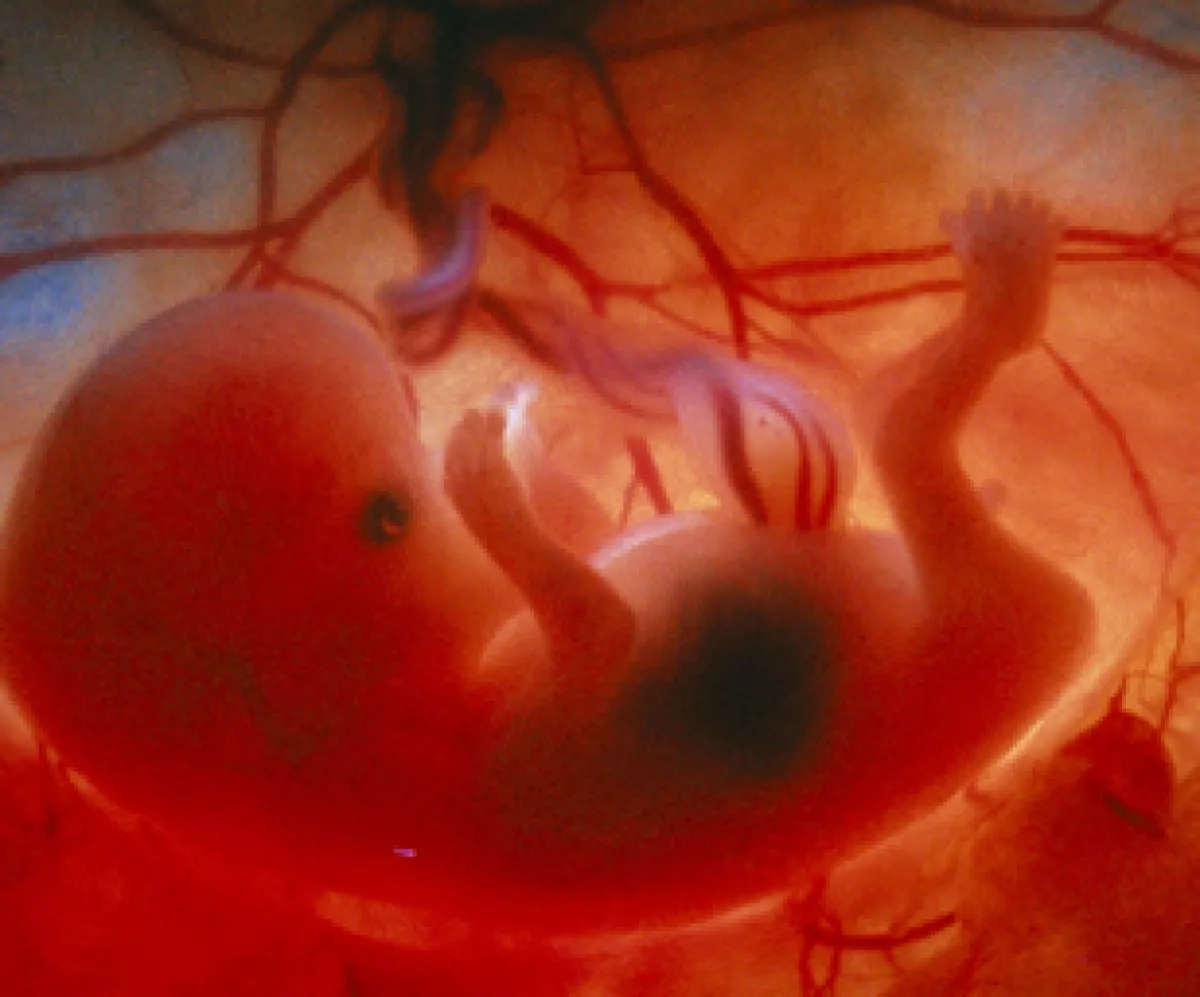

Эмбрион на 8 неделе беременности

Зародыш человека 9 недель

Человеческий эмбрион на 8 неделе беременности

Эмбрион на 8 неделе беременности

Эмбрион на 9 неделе беременности

Эмбрион Леннарт Нильсон

Человеческий эмбрион 10 недель

Эмбрион Леннарт Нильсон

Месячный эмбрион человека

Ребёнок на 8 неделе беременности

Эмбрион Леннарт Нильсон

Зародыш на 9 неделе беременности

Эмбрион на 10 неделе беременности

Эмбрион на 8 неделе беременности

Леннарт Нильсон снимки в утробе